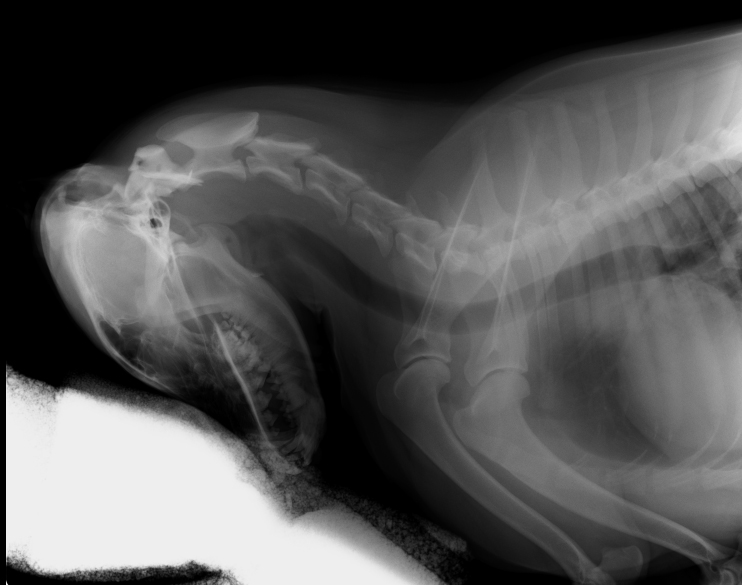

Pani mówi, że zasadniczo kości mam podobne do tych człowiekowych. Ciekawostka dla tych którzy nie wiedzą, wszystkie ssaki od myszki przez ludzi po żyrafę czy słonia mają siedem kręgów szyjnych. Matka natura potrafi być niesamowita :)

Pani doktor od rehabilitacji powiedziała, że wszystkie moje objawy świadczą o tym, że mam uraz odcinka szyjnego. Tak więc dogipsowała mnie po same uszy :( teraz jak się położę na boku to ledwo wstaję bo tak mam usztywnioną szyję.

Jeżeli nie miałbym tego usztywnienia to byłaby duża szansa na poważniejszy uraz wiążący się nawet z paraliżem przednich łapek.

To co mi dolega to coś w rodzaju wcześnie wykrytej przepukliny kręgosłupa. Wcześnie wykrytej, tzn jeszcze nieoperacyjnej, a dającej się wyleczyć właśnie za pomocą usztywnienia oraz rehabilitacji.

Patrząc na obrazek na którym namalowany jest kręgosłup to mnie dotyczy faza początkowa. Właśnie dlatego mam gips, żeby usztywnić szyję. Dzięki temu, że nie mam jak nią poruszać ustrojstwa zwane makrofagami odbudowują to co się zepsuło w mojej szyi – niestety trwa to trzy tygodnie. Żeby przyspieszyć cały proces regeneracji mam zabiegi zwane magnetoterapią (inaczej pole magnetyczne). To akurat już jest całkiem spoko, bo leżę tylko przez 30 minut :)